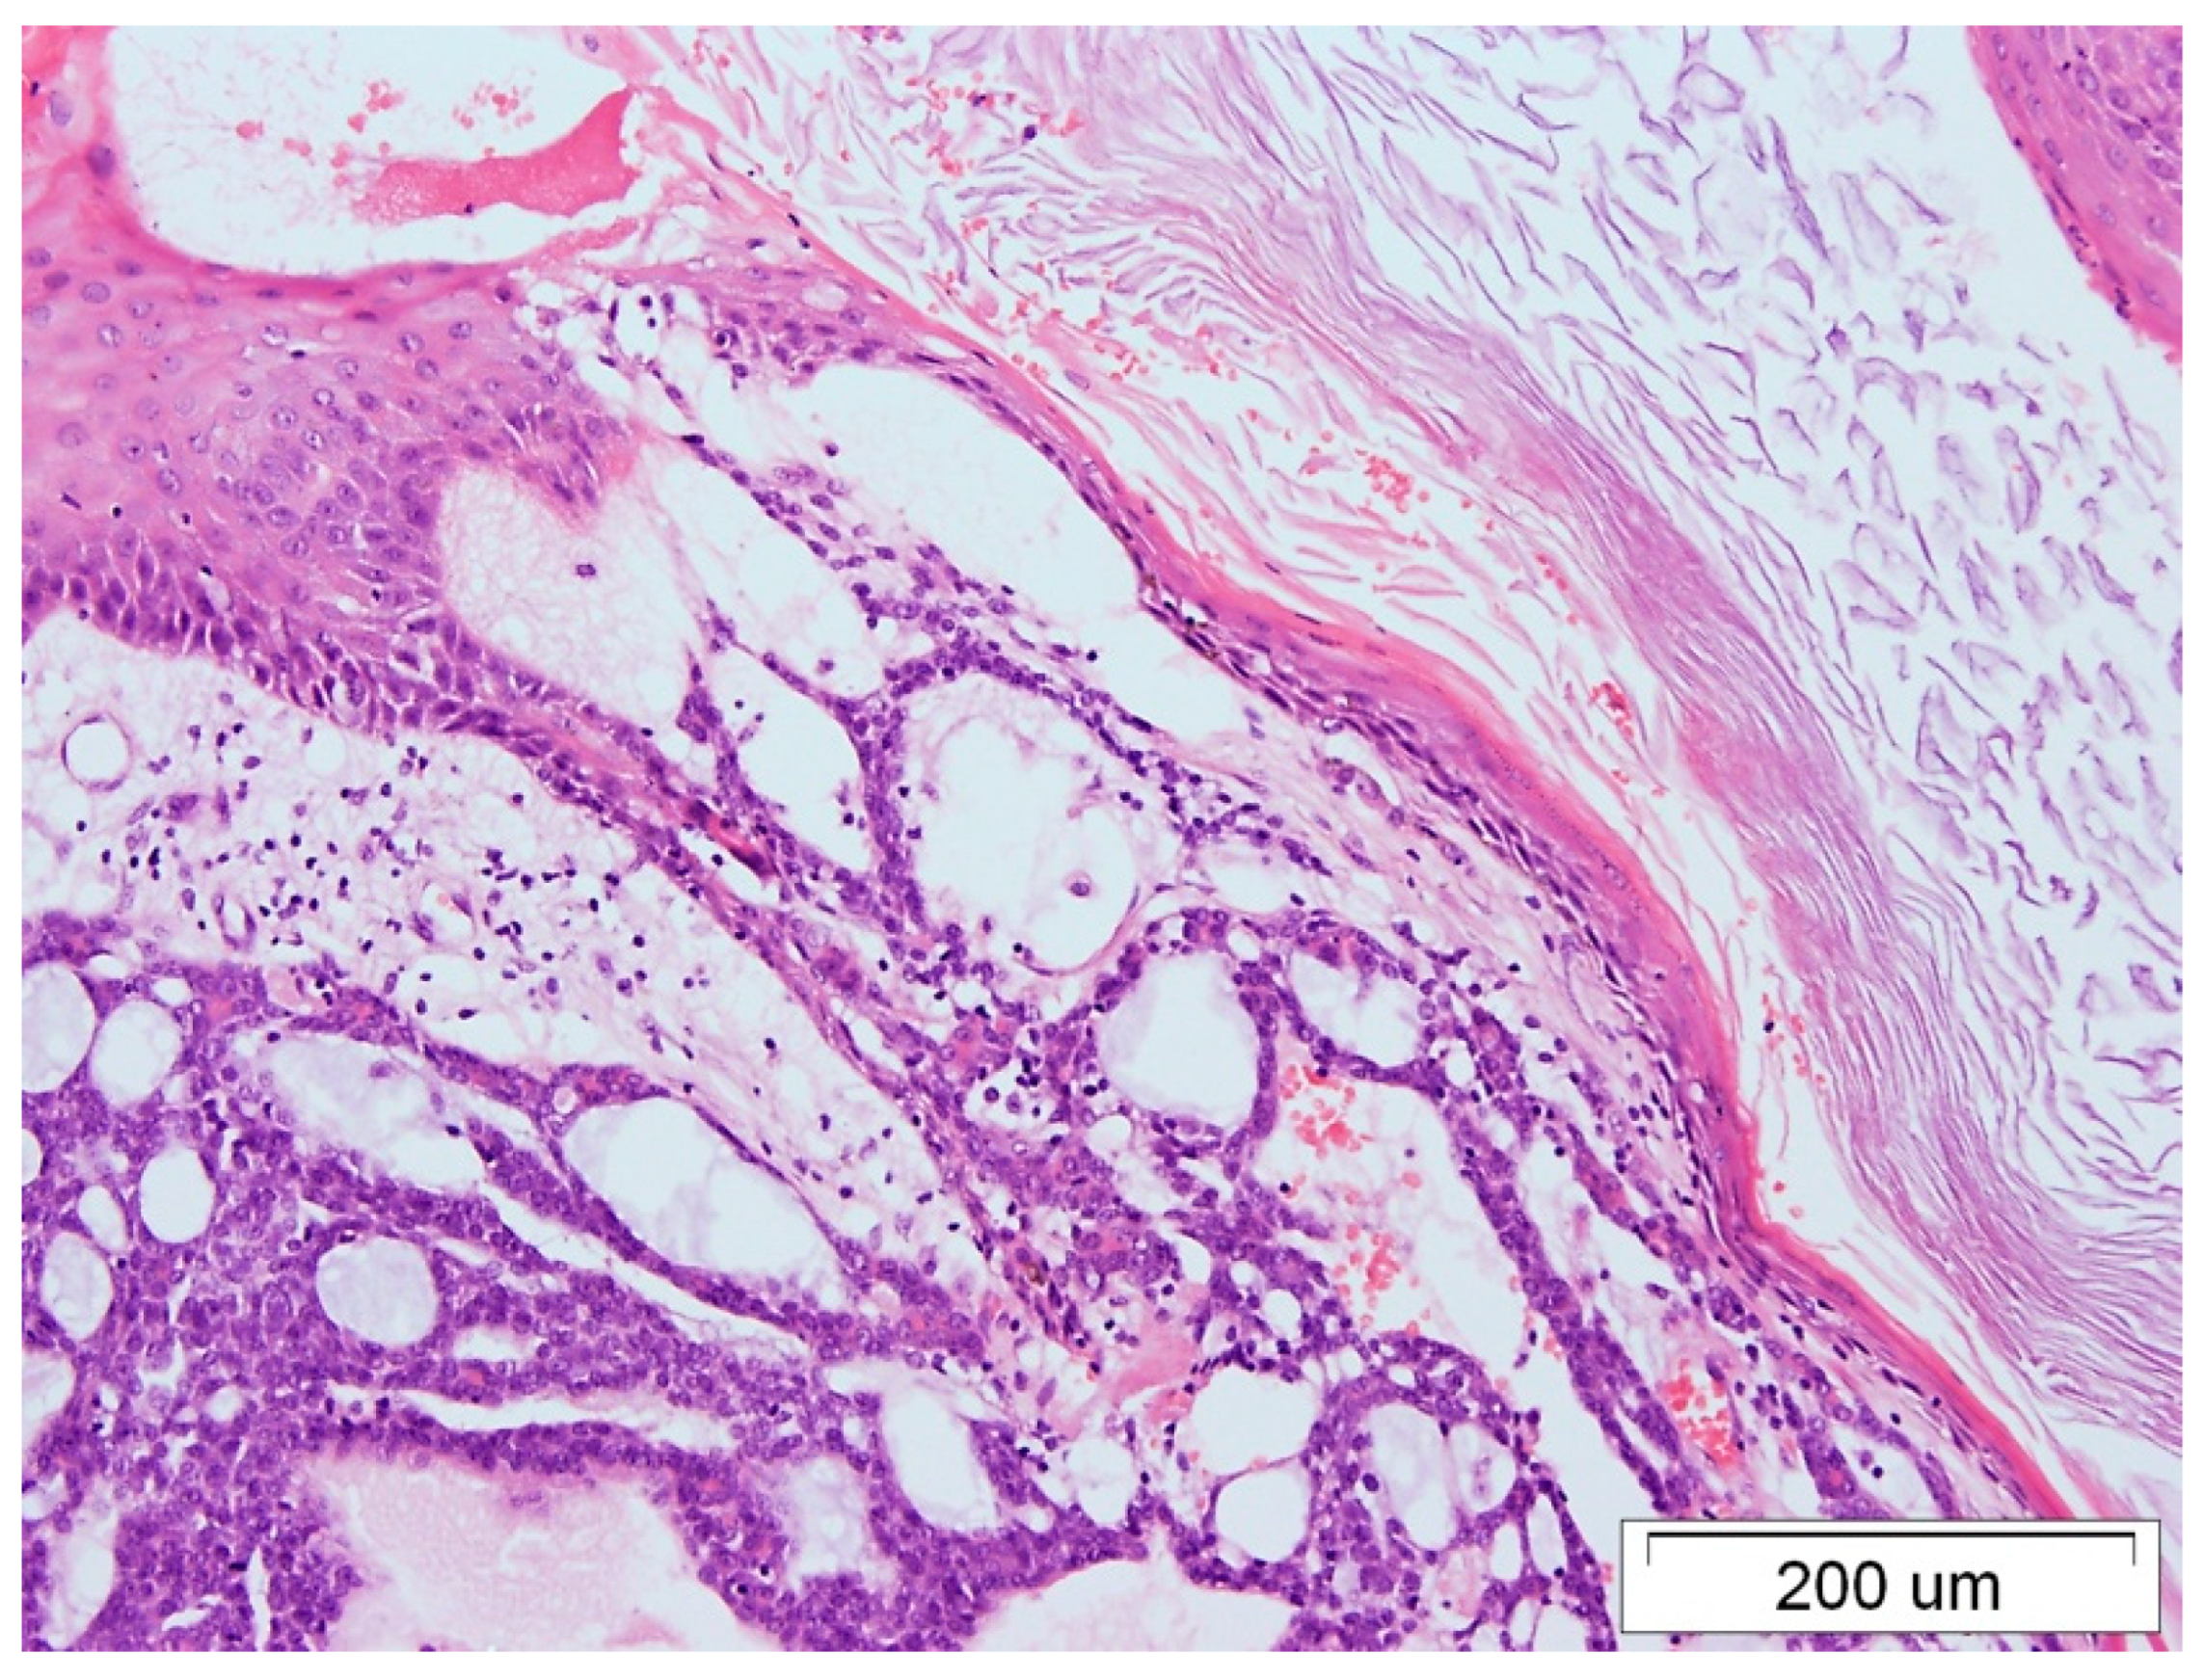

3. Case Report